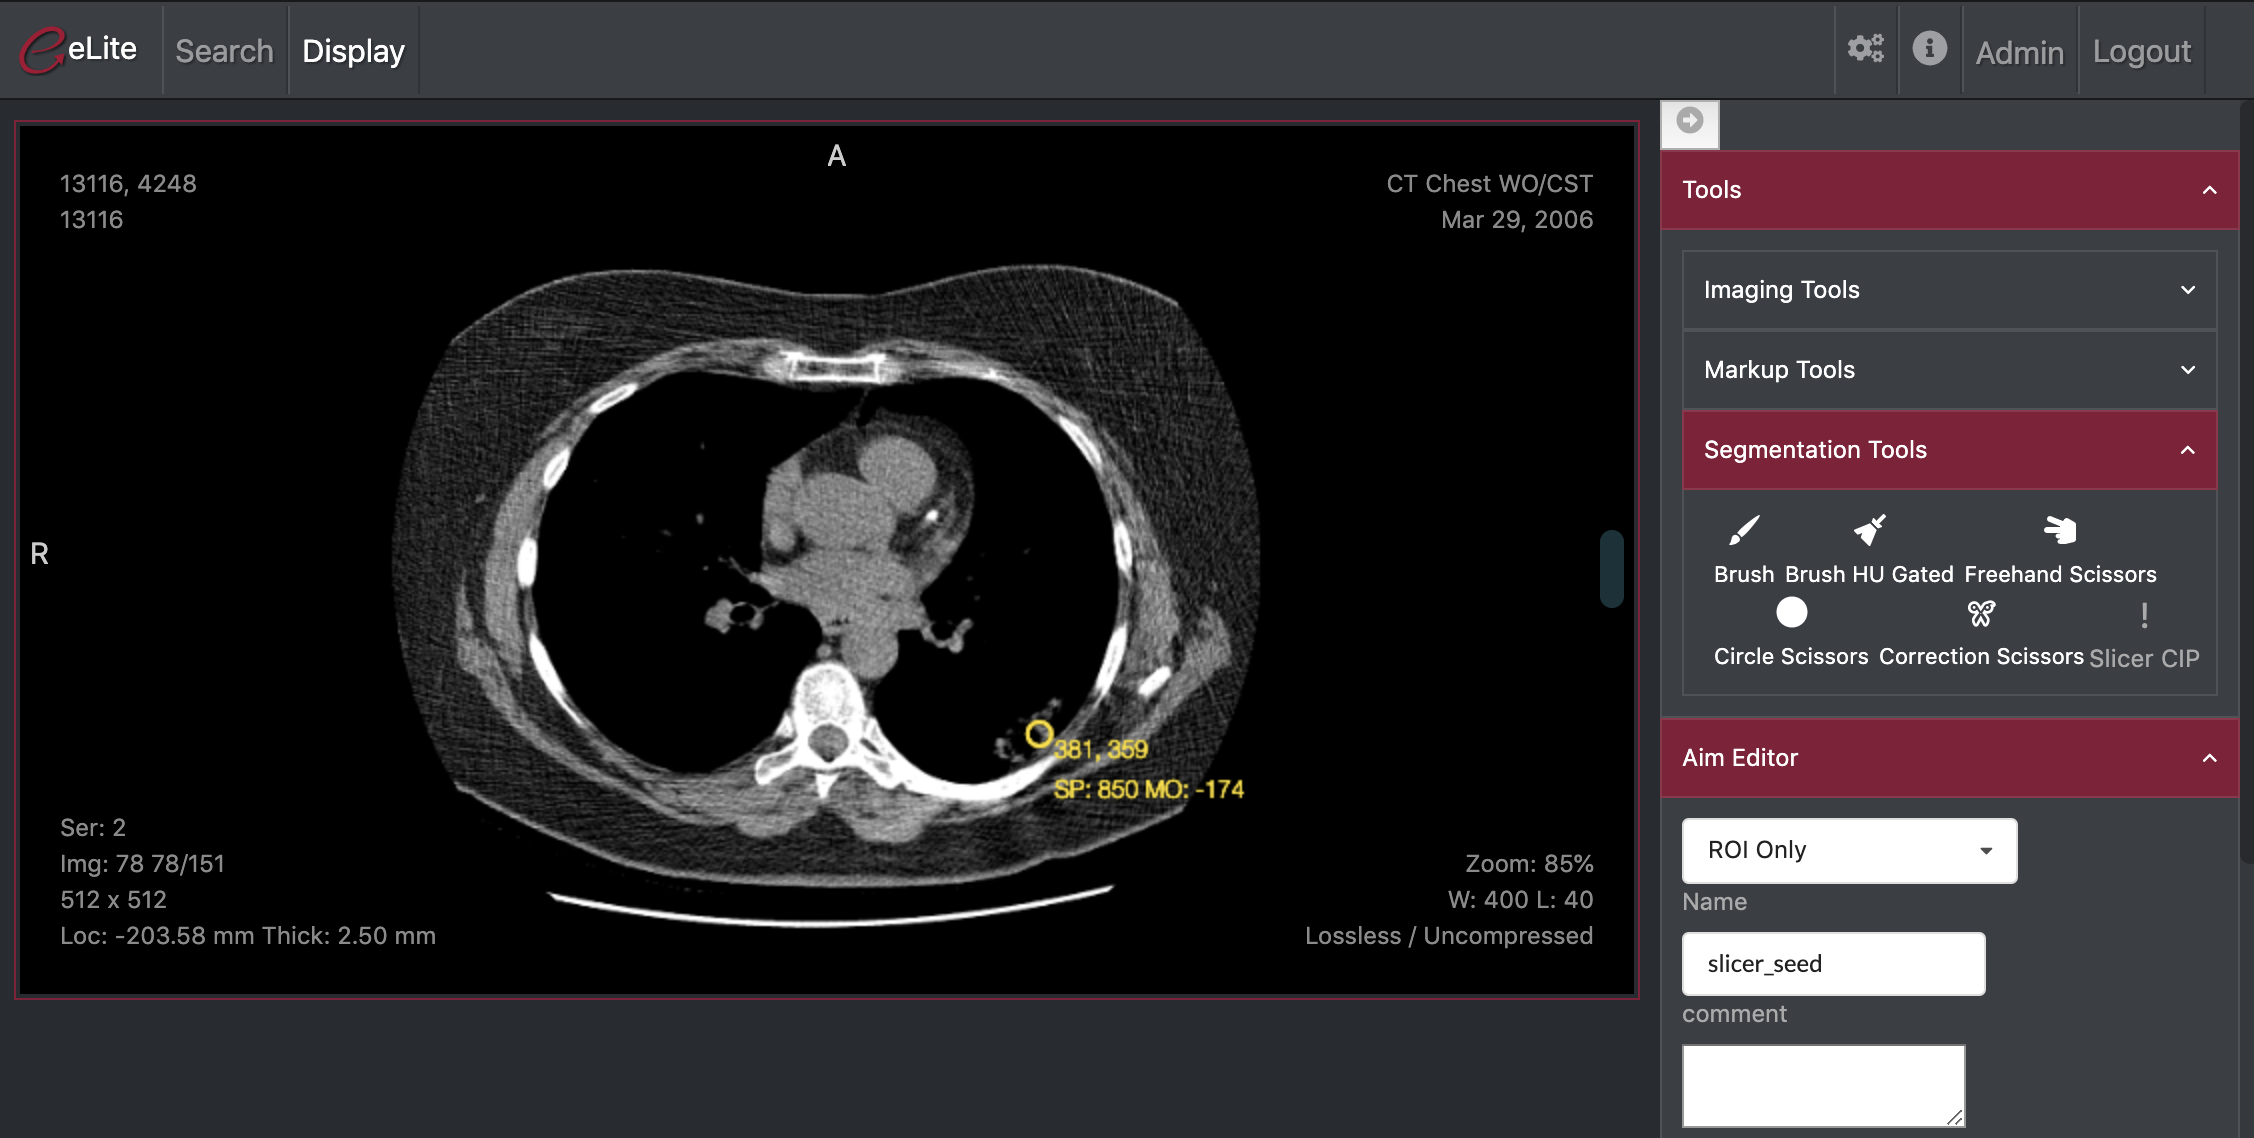

ePAD/Slicer Bridge and Segmentation Plugin

Open dockerized Slicer from ePad, open segmentation plugin and save the segmetation back to ePad

- Trigger openning dockerized Slicer from ePad

- Open the series in Slicer

- Open segmentation plugin

- Send the segmentation back to dicomweb server

- Trigger Slicer CIP plugin

- Generate Slicer Chronicle JSON to trigger CIP and send to segmentation-server

Illustrations